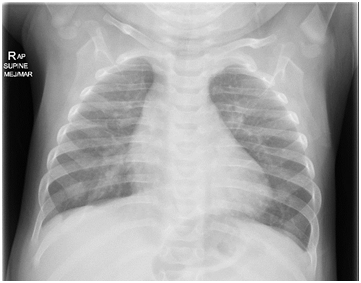

Angiography at the beginning of the cath showed that the PDA had completely disappeared (Figure 3).

Figure 3 Angiogram in the Aorta showed that the PDA disappeared.